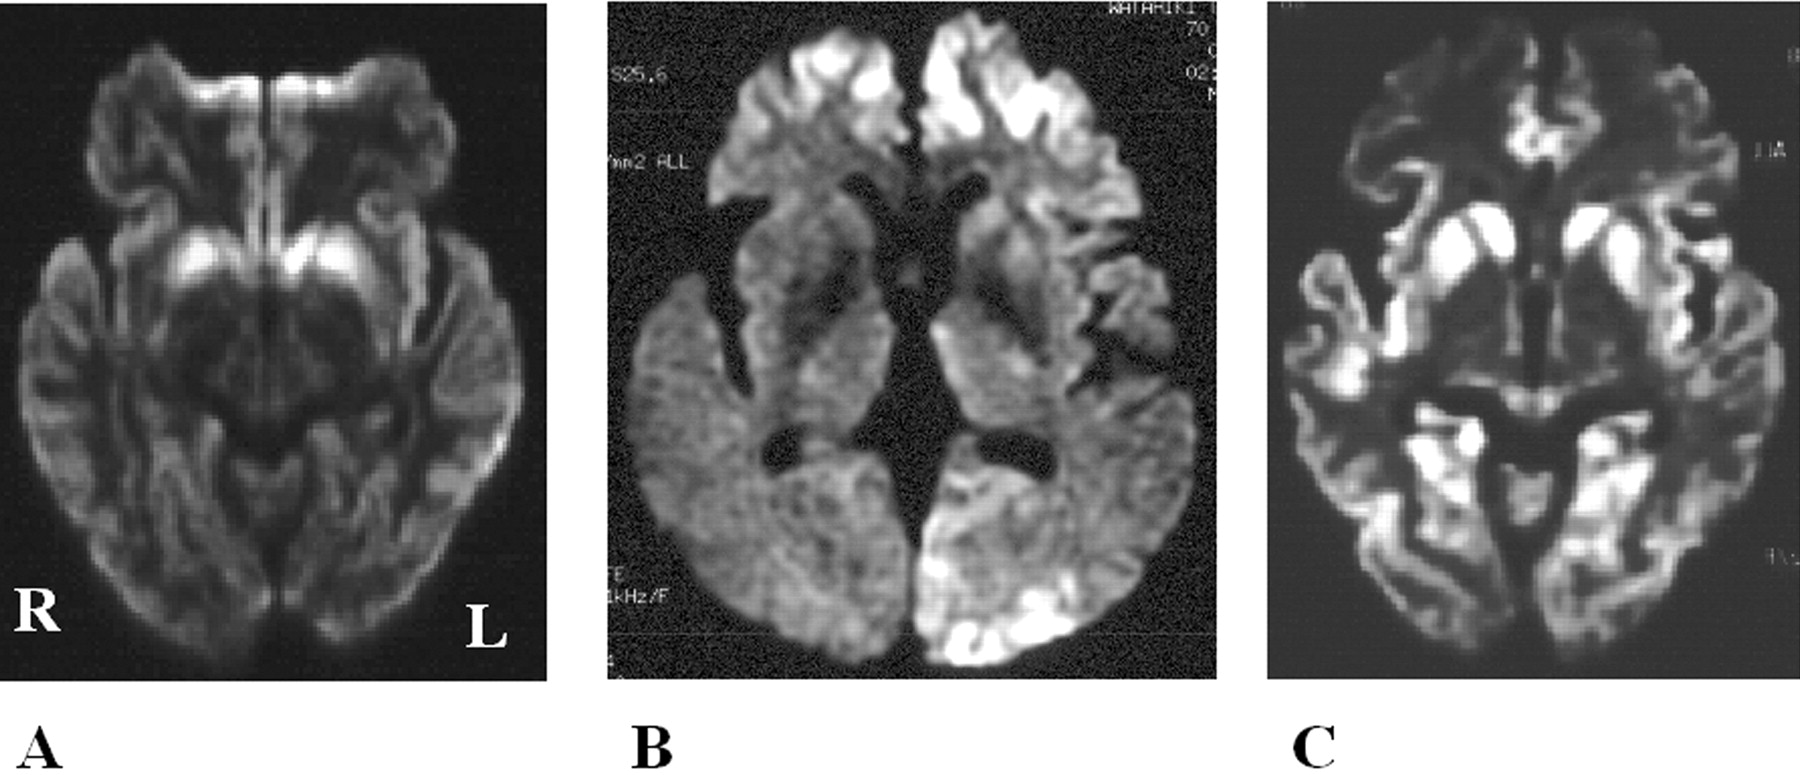

酒后驾驶是在26日检查库贾氏症患者发病后3到25周平均持续时间为10.7周。24库贾氏症患者表现出高强度脑损伤的驾车考试。两个观察者,醉酒驾车的库贾氏症诊断的敏感性为92.3%。interobserver协议率为100%。3例(12.5%)显示只在尾状头和硬膜损伤,10例(41.7%)患者显示线性损伤只有在大脑皮层,和11例(45.8%)患者显示病变基底神经节和大脑皮层(图1)。其中,只有三个病人(12.5%)显示,丘脑病变。没有病人显示高强度在小脑病变。高强度损伤在驾车之前出现脑萎缩。病变包括纹状体初并不总是对称的但是后来对称(图2),尽管对称的纹状体病变是众所周知的在库贾氏症。11在某些情况下,高强度损伤与连续驾车并不总是进展的疾病,而有时信号强度降低了疾病进展的一些病变。在某些情况下,皮质高信号强度不同,解剖分布(图3)。在终端阶段与深刻的脑萎缩,高强度损伤变得不清楚。T2I DWI-examined 26日在23日检查病人,但T2I扫描被排除在外,因为低质量由于运动构件。一位观察家认为11 22患者阳性(50.0%),而另一个观察者认为8阳性(36.4%)。interobserver协议率为68.2%,低于酒后驾车(p< 0.005)。在这两个观察者,醉酒驾车是比T2I更敏感(p一个观察者,< 0.005p另一个观察者p < 0.0005)。天赋是17 26患者的检查。一位观察家认为10 17例阳性(58.8%),和另一个观察者认为7是积极的(41.2%)。interobserver协议率为82.4%,也低于酒后驾车(p< 0.05)。醉酒驾车是比天赋更敏感(p一个观察者,< 0.01p另一个观察者p < 0.0005)。我们在图4一个例子中,只有醉酒驾车可以检测高强度异常病变。

图3。按时间顺序的改变皮质病变的零星克雅二氏症(sCJD)。皮质高强度在sCJD随着时间的推移而改变的情况下,增加和减少信号强度在不同的地区。高强度的双边枕叶皮层(A)减少(C,箭头),而信号强度在左岛和颞皮层(A)明显增加(C,箭头)。(一)和(C)之间的间隔是1个月。右颞叶皮层的高强度和双边枕叶皮层(B)减少(D,箭头为左颞叶皮层和箭头双边内侧枕叶皮层)。(B)和(D)之间的间隔是1个月。注意,高强度损伤中描述diffusion-weighted成像并不是简单地扩大疾病的进展。